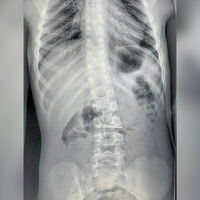

Врачи Детского центра имени Л.М. Рошаля спасли шестилетнего мальчика, который проглотил иголку. Об этом сообщили в пресс-службе минздрава Московской области.

Маленького пациента доставили в больницу на скорой помощи. Обследование показало, что инородный предмет опустился в желудок ребенка.

«С помощью биопсийных щипцов эндоскописты переместили иголку из двенадцатиперстной кишки в желудок, откуда уже безопасно извлекли из тела ребенка», — рассказали в пресс-службе ведомства, добавив, что на манипуляцию врачам потребовалось полчаса.